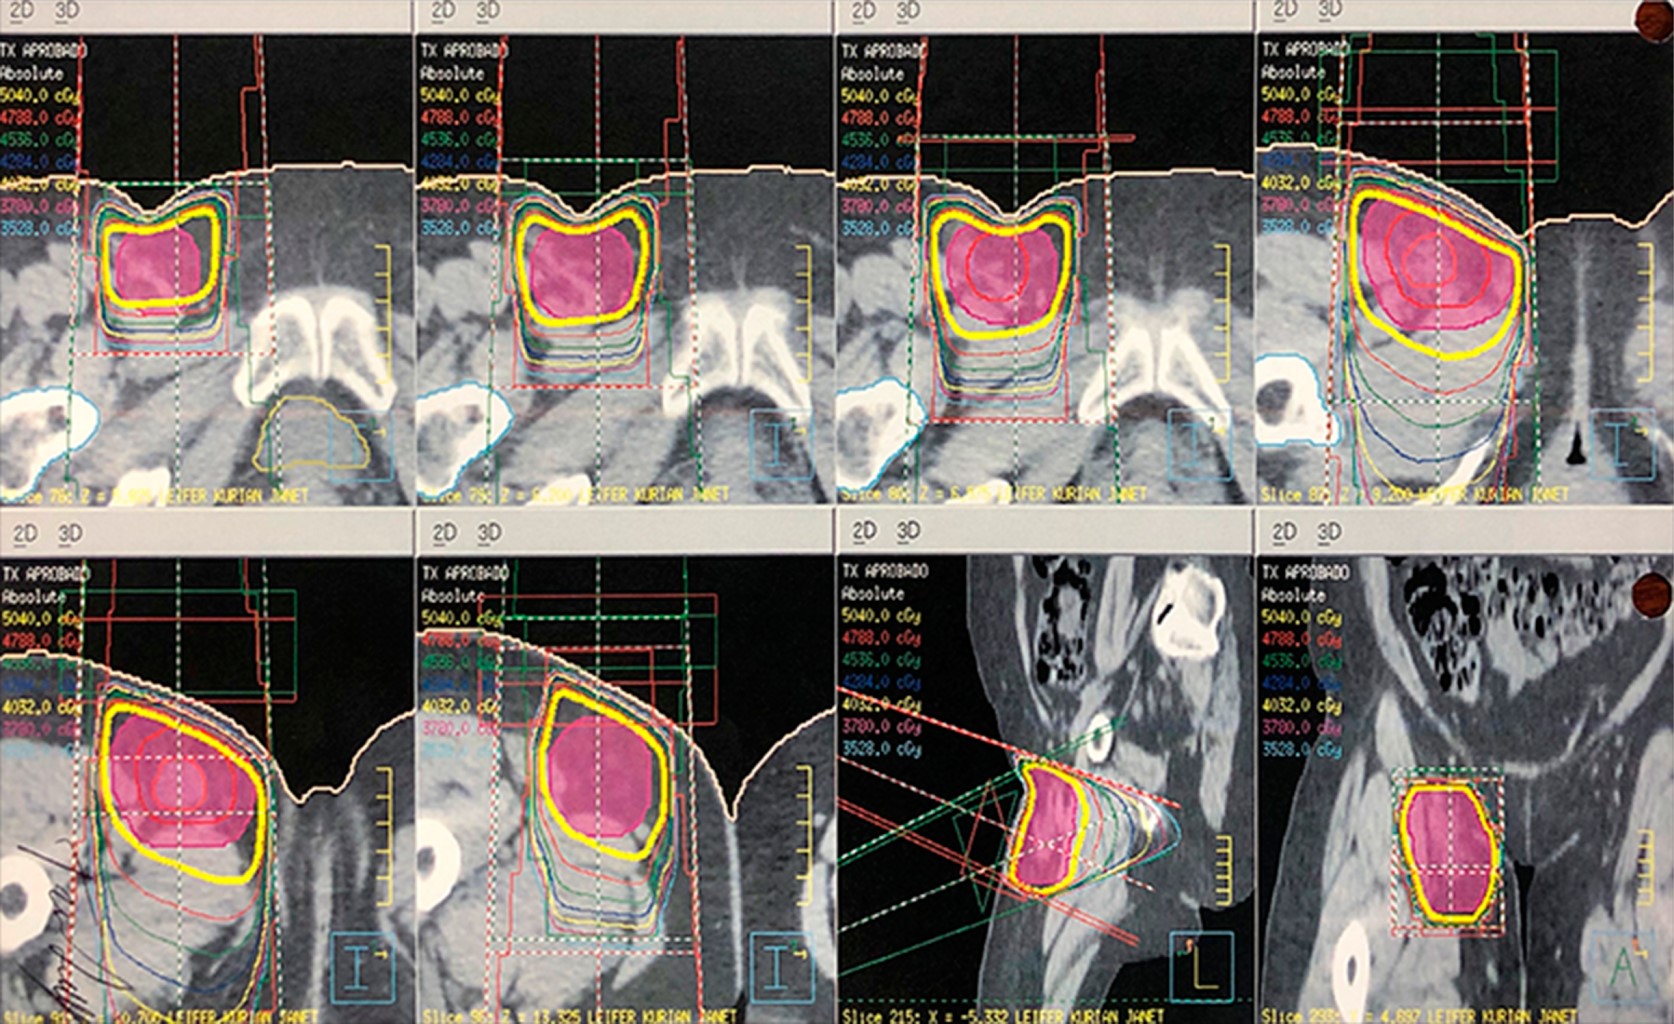

Mujer de 70 años de edad sin antecedentes médicos de importancia. Un mes previo al diagnóstico detectó una tumoración en la ingle derecha de crecimiento progresivo y acelerado. Acudió con un médico, quien ante los hallazgos sospechó de un tumor maligno y solicitó PET CT, el cual mostró una imagen sugerente de masa de tejidos blandos en la región inguinal derecha de 45 mm en su eje corto que refuerza con la aplicación de medio de contraste, alternando con imágenes hipodensas en su interior, con adecuada interfase con los músculos adyacentes, la cual tiene SUV máximo de 9.8 y en la adquisición tardía SUV máximo de 10.6. Fue sometida a resección de la lesión y el estudio histopatológico reveló linfangioleimiomatosis con tumor neuroectodérmico primitivo (sarcoma de Ewing), CD99 positivo, con bajo índice de proliferación. Márgenes quirúrgicos negativos. Se realizó una segunda revisión por parte de patología y se corroboró lo anterior, ganglio linfático infiltrado por tumor neuroectodérmico primitivo/sarcoma de Ewing. Después fue enviada para valorar RT postoperatoria. De acuerdo con la información existente se consideró candidata al tratamiento, por lo que brindamos RT conformada al sitio original del tumor (previa fusión con PET CT prequirúrgico) con márgenes para CTV de 1.5 cm y para PTV de 0.5 cm. La dosis prescrita fue de 50.4 Gy en 28 fracciones (1.8 Gy/fracción) (Figura 1). Durante la administración de la radioterapia no hubo toxicidad relacionada con el tratamiento. Actualmente la paciente tiene una supervivencia libre de enfermedad de 45 meses y no hay toxicidad debido al tratamiento. En el último PET CT de control no hay datos de recurrencia de la enfermedad (Figura 2).

Figura 2